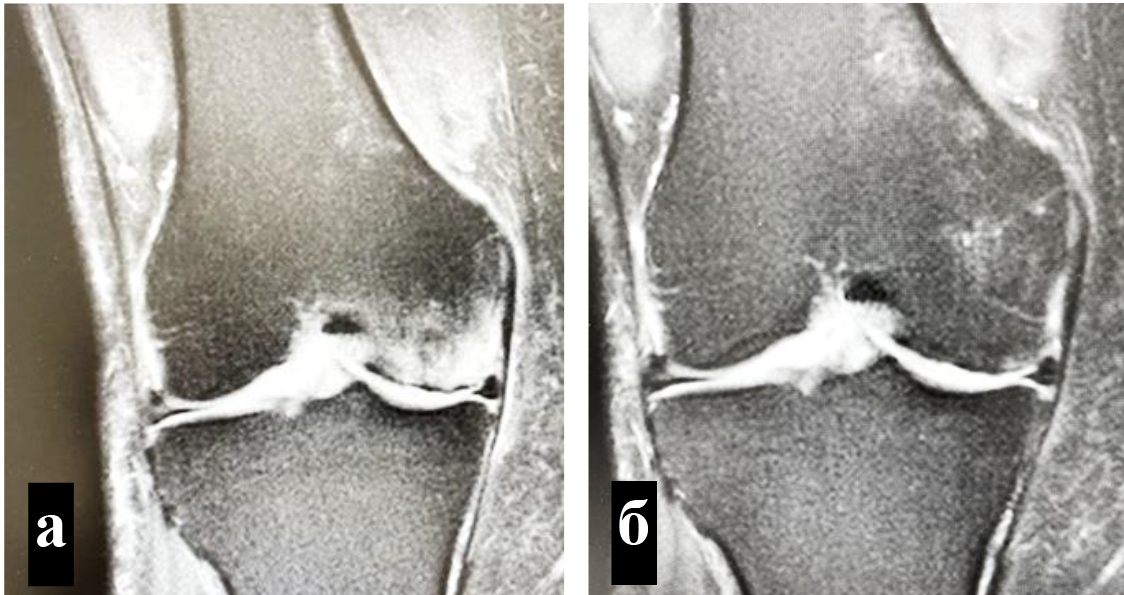

Критериями включения в научное исследование являлись: первичный ОА коленного сустава II или III стадии по классификации K-L, наличие зон трабекулярного отека костного мозга в области мыщелков бедренной или (и) большеберцовой костей по данным МРТ, интенсивность болевого синдрома не менее 6 баллов по визуальной аналоговой шкале (ВАШ), недостаточная эффективность проведенного ранее консервативного лечения.

Для определения локализации и распространенности перегрузочного отека костного мозга всем пациентам выполняли МРТ. На Т1-взвешенных изображениях визуализировали снижение интенсивности сигнала, на Т2-взвешенных изображениях с жироподавлением и на коротких последовательностях «восстановления – инверсии» (STIR) выявляли высокую интенсивность сигнала (рис. 1).

Объективным показателем регресса болевого синдрома и нормализации клеточного метаболизма субхондральных структур являлось значительное сокращение объема или вовсе исчезновение зон трабекулярного отека костного мозга, что подтверждалось уменьшением гиперинтенсивных участков по данным МРТ (рис. 4) [8].